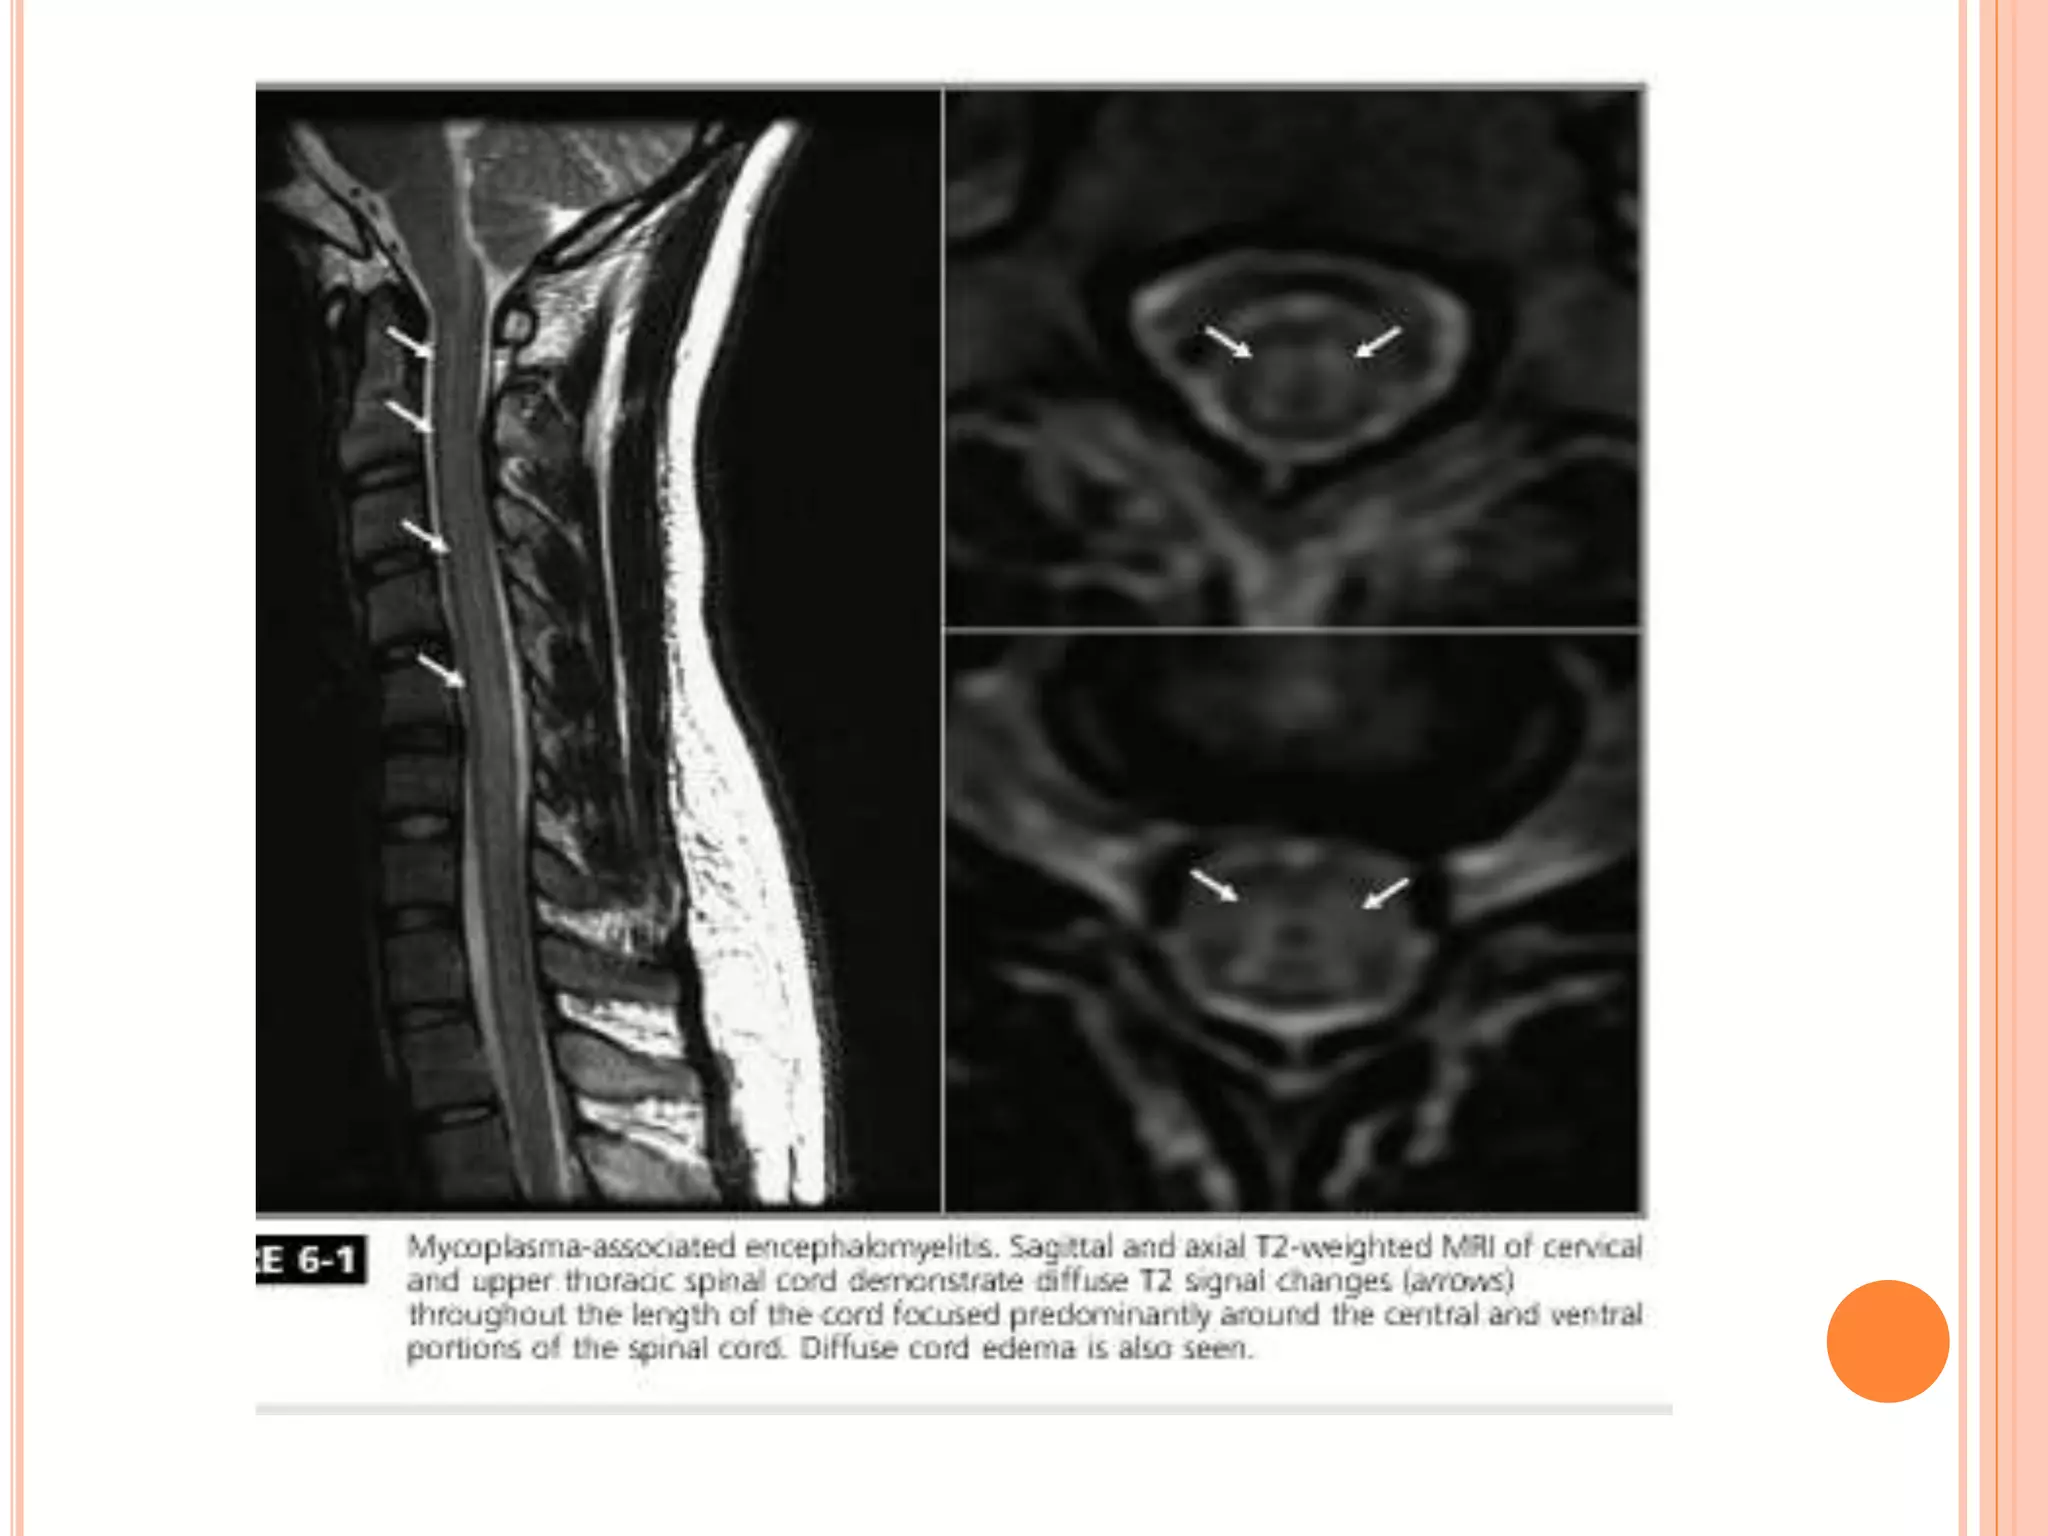

 Whipple disease-

Mycoplasma

 Mycoplasma